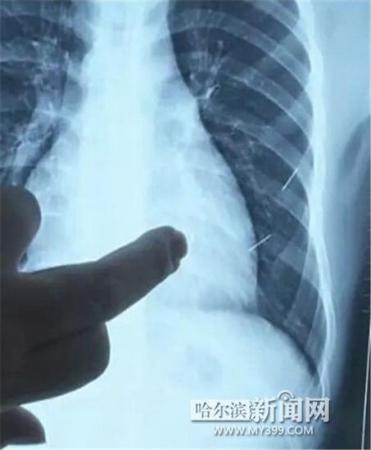

醫(yī)生指出X光片上的針狀物

昨日上午,記者在哈醫(yī)大二院第八住院部心外三病房找到了躺在病床上痛苦不堪的董立仁,家屬正在他身旁不斷安慰著他。見記者前來,董立仁母親李百燕拿出一張X光片,上面可以清晰地看到胸腔內(nèi)一共有4根針狀物,其中一根在心臟部位,兩根在胸腔壁上,還有一根在腹腔壁上。

心外三病房董立仁的主治醫(yī)生告訴記者,董立仁送到醫(yī)院時(shí)病情很危險(xiǎn),隨時(shí)可能危及生命。“通過檢查發(fā)現(xiàn),他心臟內(nèi)有一個(gè)金屬異物,正好在心臟上。心臟每次跳動(dòng)都與其產(chǎn)生摩擦,導(dǎo)致出血,心包積液懷疑是血液。如果大量出血會(huì)凝結(jié)成血塊,血塊包裹住心臟就會(huì)影響心臟跳動(dòng),隨時(shí)都有停跳的危險(xiǎn)。心臟上的異物是致命傷,其余胸腔壁和腹腔壁的異物傷害不大?!?/p>

昨天16時(shí)30分左右取針手術(shù)開始。因鋼針隨時(shí)會(huì)危及患者生命,此次手術(shù)定義為大型手術(shù)。開胸后,醫(yī)生打開董立仁心包,發(fā)現(xiàn)一枚鋼針已深深扎入心臟,僅露出1厘米長度在外。拔出鋼針后,醫(yī)生發(fā)現(xiàn),這枚針長達(dá)5厘米。受鋼針影響,心包出現(xiàn)大量積液,近800毫升。

隨后,在下胸壁位置,第二枚鋼針順利取出。在尋找另兩枚鋼針過程中,普外、胸外多名醫(yī)生也參與手術(shù),為主刀醫(yī)生提供更為穩(wěn)妥的處理建議。根據(jù)X光片顯示位置,醫(yī)生未在患者體內(nèi)找到剩余兩枚鋼針。醫(yī)生懷疑,其中一枚鋼針可能深藏在肋骨骨膜位置,無法尋找,最后決定結(jié)束手術(shù),做進(jìn)一步觀察,研究下一次手術(shù)方案。